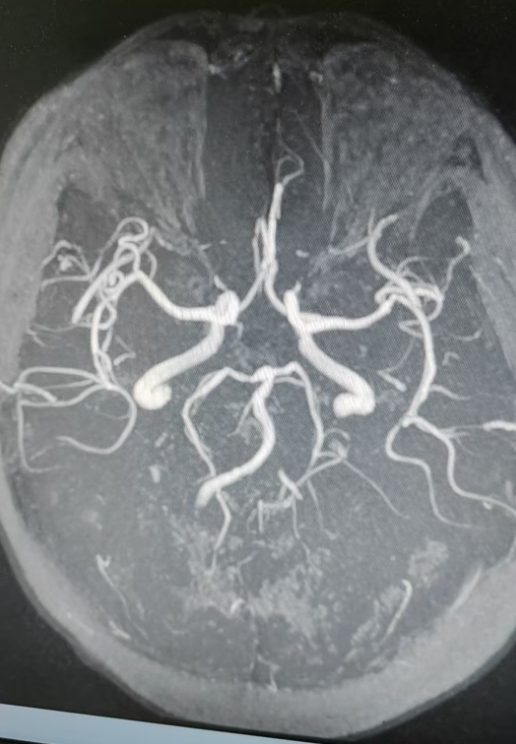

经颅多普勒超声及颅脑MR平扫+DWI+MRA检查显示:颅骨及颅外软组织未见异常,脑灰白质分布正常;两侧侧脑室旁、基底节、左侧丘脑、脑桥可见斑点状、小片状异常信号,部分区域伴脑软化及周围胶质增生;两侧额顶叶、侧脑室旁白质存在脑白质脱髓鞘改变,并伴有增龄性脑萎缩;同时提示部分空泡蝶鞍,两侧上颌窦、筛窦粘膜增厚;脑血管方面,存在脑动脉硬化,左侧大脑中动脉M2段、大脑后动脉P3段等多部位血管局部变窄,基底动脉远端局部开窗,左侧椎动脉未显示。结合检查结果与病史,患者转入内二科(神经内科·肾病)进一步救治。

正是这次检查,发现他:1.左侧椎动脉狭窄;2.不完全性偏瘫3.多发腔隙性脑梗死4.高血压病3级(很高危)5.2型糖尿病伴周围血管病。

颅脑MR平扫+DWI+MRA检查

经综合评估,团队一致认为需要行血管内介入治疗,意见明确:拟实施“全脑血管造影右侧椎动脉V4段球麻醉方式囊扩张+支架植入”。

术中,医护团队精准操作,顺利完成全脑血管造影右侧椎动脉V4段球麻醉方式囊扩张+支架植入等关键步骤。手术顺利,患者安返病房,医护团队密切监测其病情变化,给予针对性护理及对症治疗。

术后,复查双侧椎动脉造影显示,血管鞘在股动脉内位置良好,缓慢拔出血管鞘,Starclose闭合器闭合股动脉满意,病变血管已成功“疏通”。